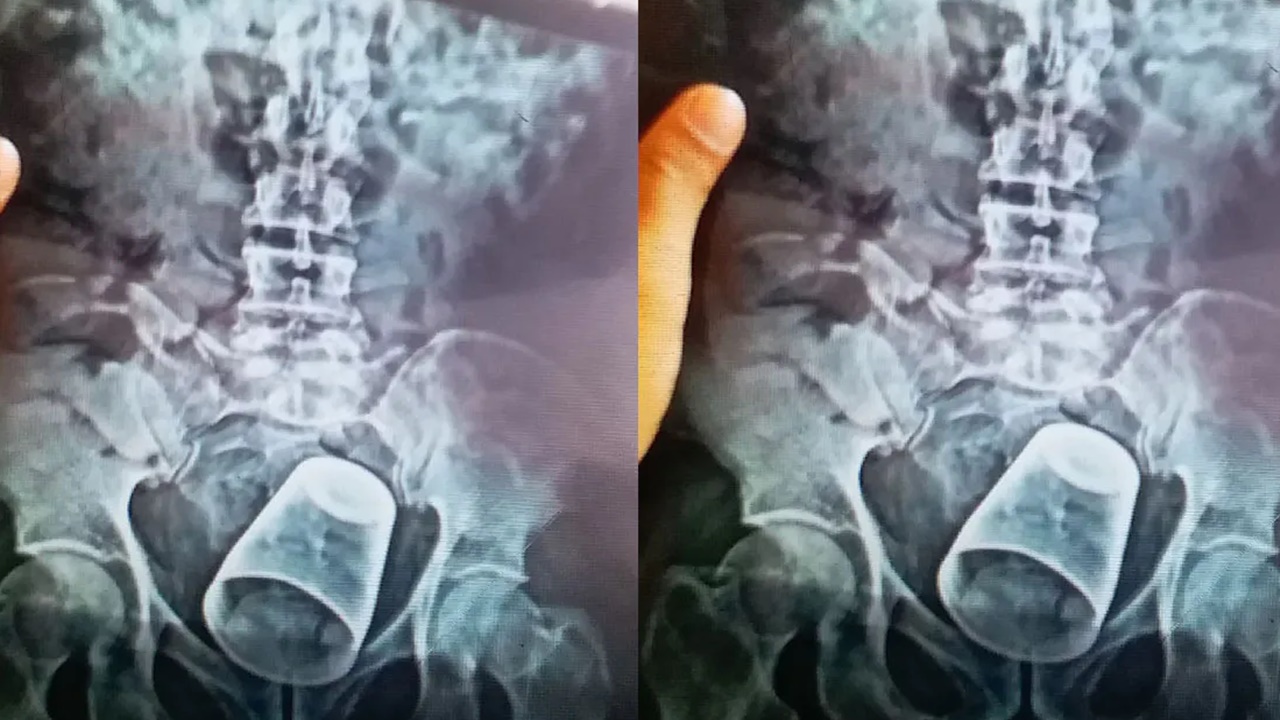

బిహార్ పాట్నాలోని పీఎంసీహెచ్ ఆస్పత్రిలో అరుదైన శస్త్రచికిత్స జరిగింది. ఓ వ్యక్తి ప్రైవేటు భాగాల్లో స్టీల్ గ్లాస్ ఇరుక్కుంది. ఈ షాకింగ్ ఘటన నవాదా జిల్లాలో వెలుగుచూసింది. ఓ వ్యక్తి మలద్వారంలోకి స్టీల్ గ్లాస్ చొచ్చుకెళ్లింది. దీంతో అతడు నొప్పితో విలవిల్లాడిపోయాడు. వెంటనే కుటుంబసభ్యులు అతడిని పాట్నాలోని పీఎంసీహెచ్ ఆస్పత్రికి తరలించారు. తొలుత కేసు వివరాలు తెలుసుకుని డాక్టర్లు ఆశ్చర్యానికి గురయ్యారు. ఆపై పరీక్షలు చేసిన డాక్టర్లు.. మలద్వారం నుంచి గ్లాసును వెనక్కి తీయడం సాధ్యం కాదని నిర్ధారించుకున్నారు. ఎక్స్​రేలో కనిపిస్తున్న స్టీల్ గ్లాసుస్టీల్ గ్లాసు.. బాధితుడి మలద్వారంలో చాలా లోతుకు వెళ్లిందని వైద్యులు తెలిపారు. ఎక్స్​రేలో ఈ విషయం స్పష్టంగా తెలిసిందని చెప్పారు.

ఆపై డాక్టర్ వినయ్ కుమార్ నేతృత్వంలోని ఐదుగురు సభ్యుల వైద్య బృందం విజయవంతంగా ఆపరేషన్ నిర్వహించింది. పొట్టకు ఆపరేషన్ నిర్వహించి గ్లాసును బయటకు తీశారు. ఆపరేషన్ పూర్తైన తర్వాత బాధితుడిని పర్యవేక్షణలో ఉంచారు. కొద్దిగంటల తర్వాత ఐసీయూ నుంచి సాధారణ వార్డుకు తరలించినట్లు వివరించారు. గ్లాసు అతడి రహస్య భాగంలోకి ఎలా వెళ్లిందన్న విషయంపై వైద్యులు అనుమానం వ్యక్తం చేస్తున్నారు. బాధితుడికి మతిస్థిమితం సరిగా లేదని బంధువులు చెబుతున్నప్పటికీ.. అతడు తమతో మామూలు వ్యక్తిలానే ప్రవర్తించాడని వైద్యులు పేర్కొన్నారు. స్టీల్ గ్లాసును బోర్లా వేసి దానిపై కూర్చున్నట్టు అతడు చెప్పినట్లు వెల్లడించారు. వైద్యులు ఈ విషయంపై పలు అనుమానాలు వ్యక్తం చేశారు. మంత్రతంత్రాలు, పూజలను సాధన చేసేందుకే అతను గ్లాస్‌పై కూర్చొని ఉంటాడని అనుమానిస్తున్నారు. ఈ క్రమంలోనే అది లోపలికి వెళ్లిపోయిందని చెబుతున్నారు.